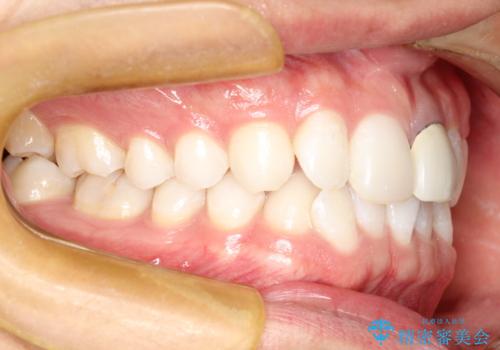

インビザラインによる矯正治療(非抜歯) 下の前歯の歯並びの改善

- 主に下の歯並びの改善を主訴としてご来院されました。

右下の犬歯と前歯が大幅に重なっているのと、歯の向きも大きく横に倒れています。この部位の正常な配列のためには、3次元的に大幅な移動が必要となりました。

インビザラインの特色を生かした歯牙移動計画を作成し、非抜歯にて治療を行いました。

概ね1年弱で治療が完了しました。

前歯の大きな3次元的移動を可能にするために、当院独自の工夫を随所に盛り込み、狙い通りの治療結果を得られました。